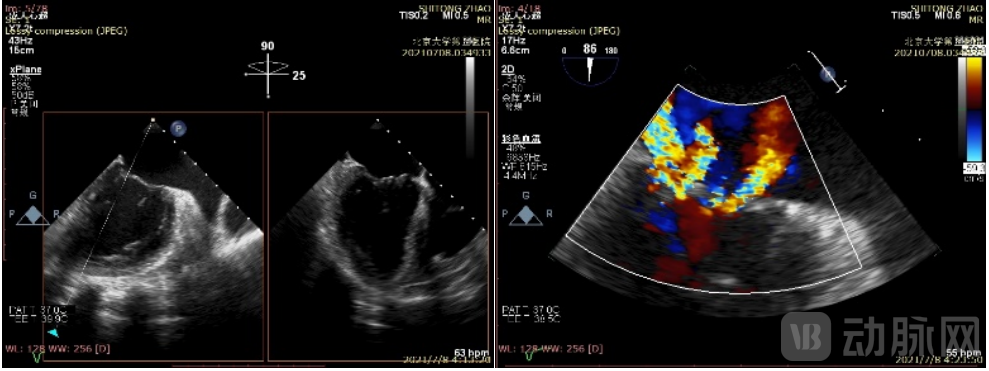

患者,男,九旬老人,心超显示重度二尖瓣反流。北京大学第三医院心脏团队经过术前讨论,认为该患者外科手术高危,对其行二尖瓣瓣膜修复术。

患者术前超声图(TEE)